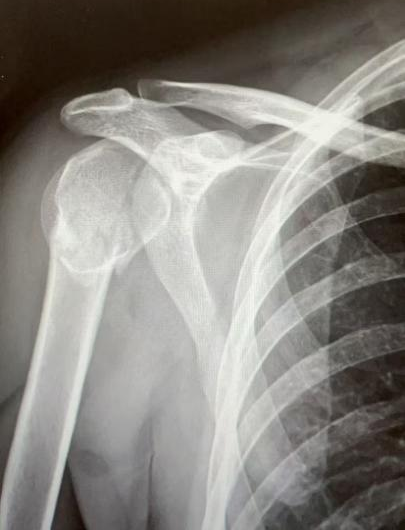

10月5日,40岁李先生摔倒致右肩部着地,8:40入院后,高峰医师团队诊断为“右肱骨近端粉碎性骨折”,13:35做好充分术前准备后历经3小时手术完成。